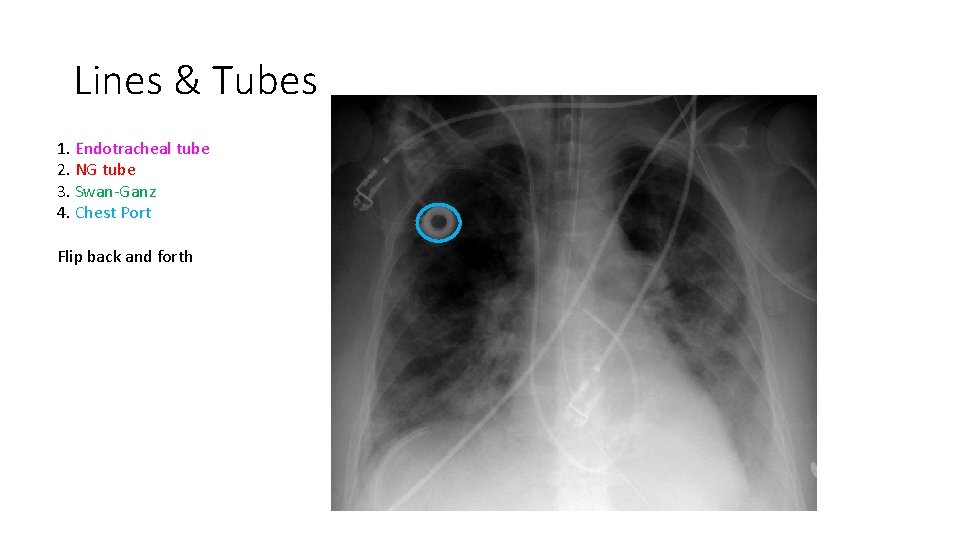

Lines & Tubes 1. Endotracheal tube 2. NG tube 3. Swan-Ganz 4. Chest Port Flip back and forth